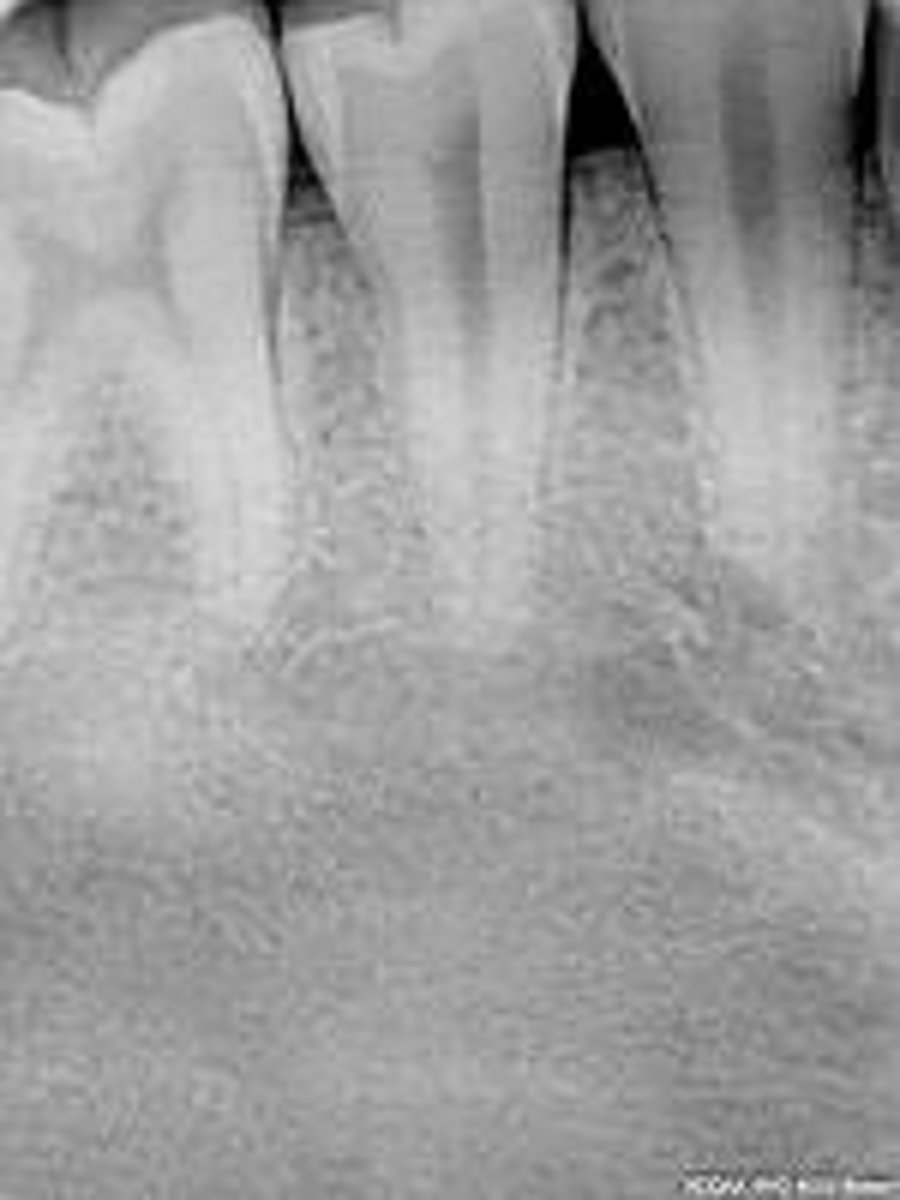

what is this?

what is this radiolucent area in the image?